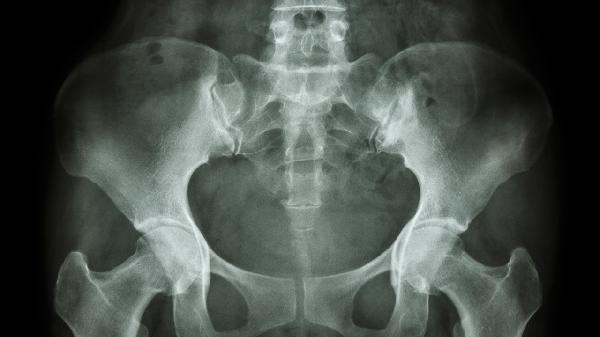

双侧股骨大转子滑囊炎怎么治疗

双侧股骨大转子滑囊炎可通过休息制动、物理治疗、药物治疗、穿刺抽液、手术切除等方式治疗。双侧股骨大转子滑囊炎通常由过度摩擦、外伤、感染、风湿性疾病、代谢异常等原因引起。